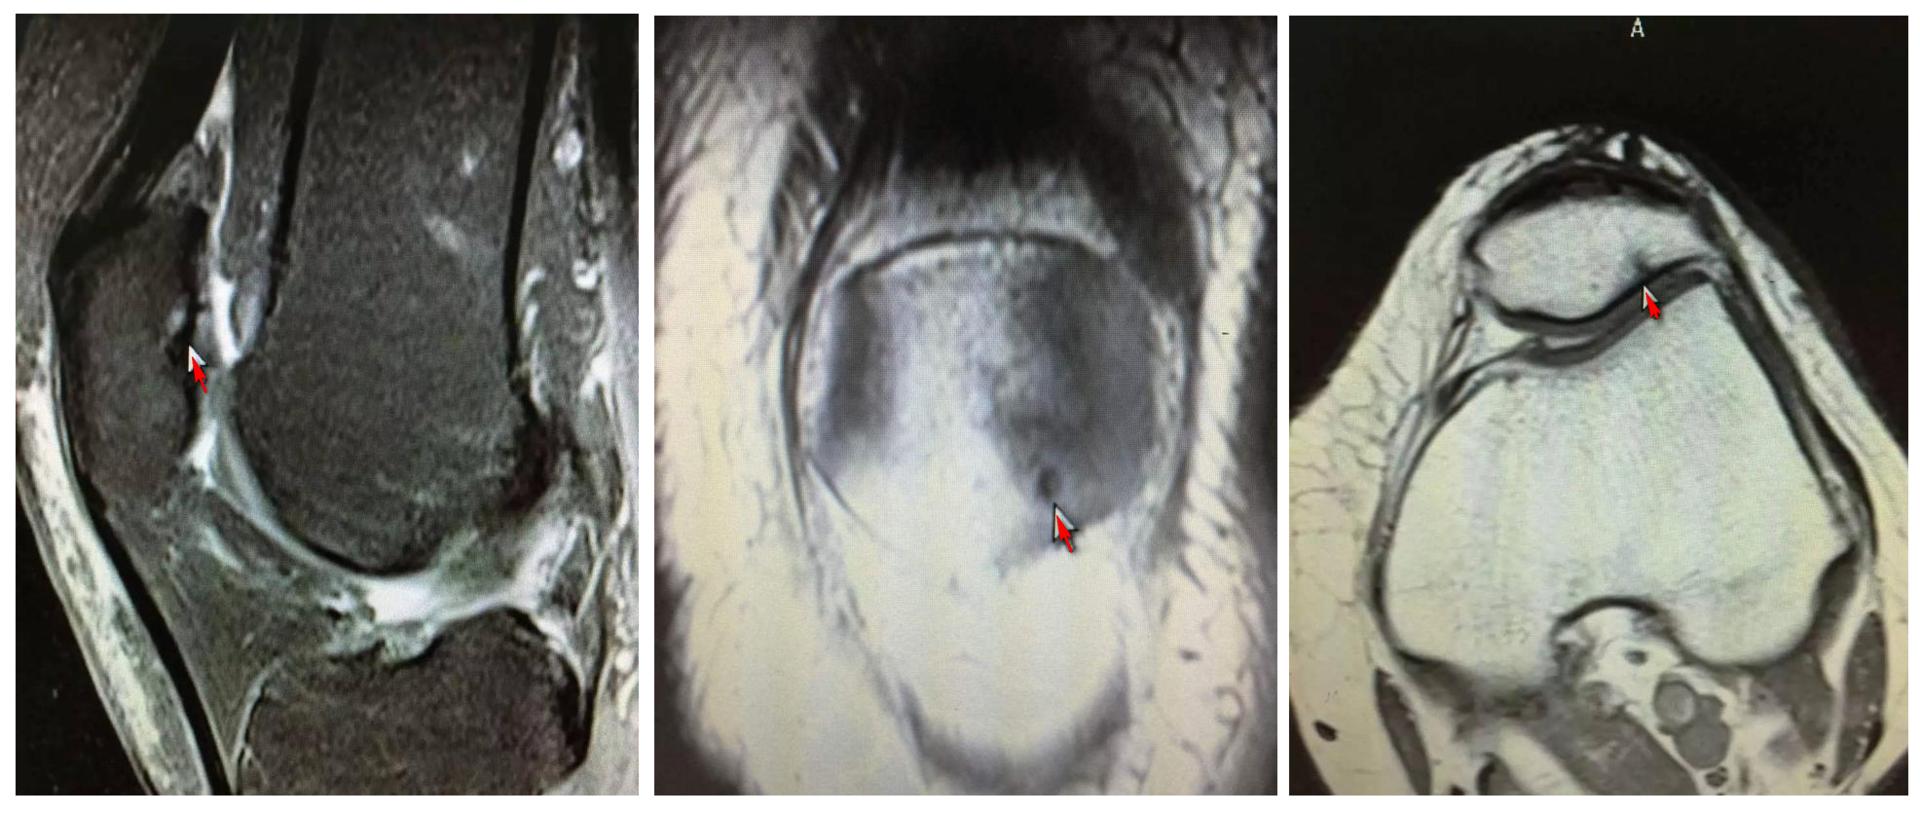

3.X线检查:

照膝关节正,侧位及髌骨切线位X线片,早期无异常所见,晚期可因软骨大部磨损,髌骨与股骨髁部间隙变窄,髌骨和股骨髁部边缘可有骨质增生。